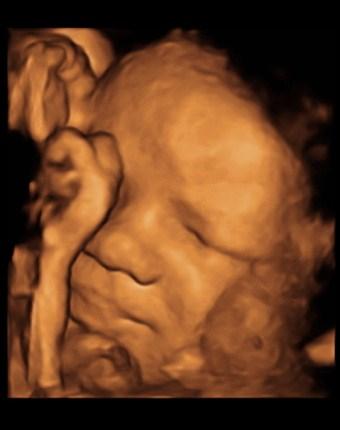

also ich hab cmv machen lassen, werde den großen zuckertest machen lassen (der kleine wird nur übernommen), strep-test am ende der ss und ggf ersttrimesterscreening. das entscheidet sich morgen. habe auch das us-paket dazu gebucht, ich finde nicht das man nicht mehr lange was sehen kann, im gegenteil, je fortgeschrittener die ss ist, desto mehr gibt es ja zu sehen :o) hänge mal ein bild von meinem sohn 36+1 mit an.

Bild zu